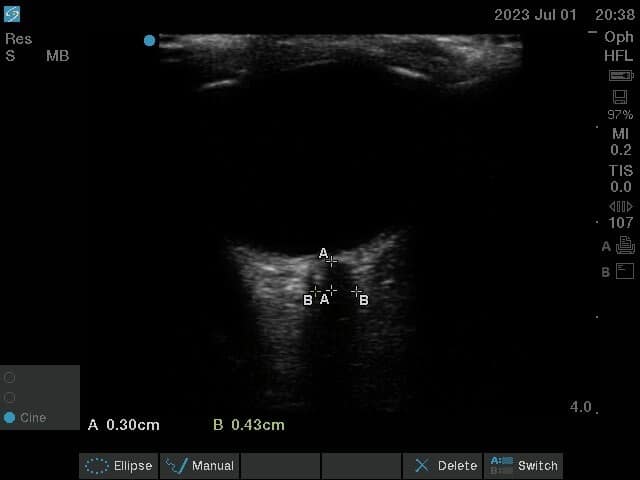

- A point 3 mm posterior to the optic disc is considered the target point. The optic nerve is considered to be most distensible and hence representative of rise in ICP at this point.

- The optic nerve is seen as an anechoic (black) linear structure bounded by hyperechoic (bright) lines, ie, optic nerve sheath at this level (behind the optic disc).

- Measurements are taken in both axes, and a mean of ONSD in both transverse and vertical axes is taken as the final measurement representative of ONSD (Figure 5).

- The cut-off values of ONSD for predicting a raised ICP vary from .48 to .59 cm in different studies. Studies that compare ONSD with invasive ICP monitoring correlate an invasive ICP of > 20 mm Hg with an ONSD of 5.7 - 6.0 mm.

A value more than 5.82 mm of ONSD confirms raised ICP with a sensitivity of 90%, a specificity of 92% and a negative predictive value of 92%. A value less than 5.3 mm of ONSD rules out raised ICP with 100% sensitivity and negative predictive value.33 However, the accuracy of measurement of ONSD may vary with probe orientation and experience of the ultrasonographer. So, a mean of ONSD values is clinically more relevant.